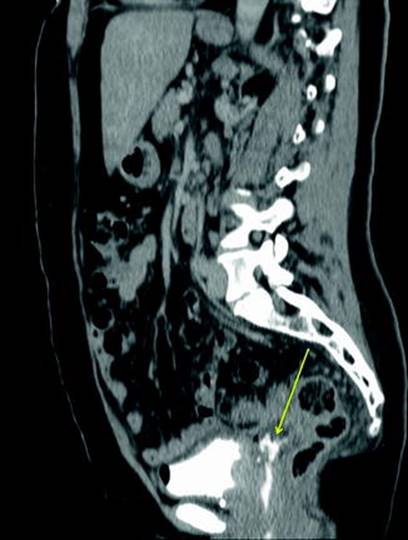

Determining the location of severe vaginal urinary leakage is often the most challenging part of an incontinence evaluation. While voiding cystourethrograms and plain cystograms can often demonstrate the presence of a fistula, they often fail to demonstrate the exact location of vesicovaginal fistulae, as well as the presence of multiple fistulae (Fig. 14.2). Additionally, ureteral injury can be present in up to 12% of cases of vesicovaginal fistulae, and recognition of this preoperatively is essential [8]. CT Urography has largely replaced intravenous pyelography as a diagnostic modality of choice when evaluating upper tract damage or fistula. Cystoscopy is an essential component in the evaluation of any woman with unexplained or continuous incontinence. Typically, cystoscopy can show a fistulous tract, or at least suggest fistula due to severe inflammatory changes (Fig. 14.3). Retrograde pyelogram at the time of cystoscopy can usually demonstrate ureteral extravasation of contrast (Fig. 14.4). Alternatively, CT Urography can show locations of urinary extravasation and often be diagnostic of ureterovaginal fistula (Fig. 14.5).

Fig. 14.5

CT Urography can be an excellent imaging modality when evaluating for presence of fistula. Here, a communication can be seen (arrow) between the distal ureter and vagina